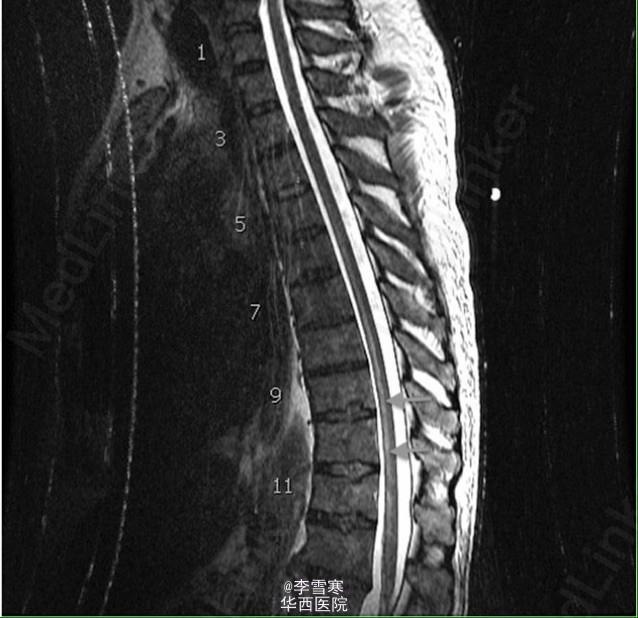

胸膜外全肺切除术后脊髓缺血

患者肺部活检为恶性胸膜间皮瘤,行胸膜外全肺切除术,术中两次低血压,术后第二天双下肢不能动弹,仅存知觉。转自网络